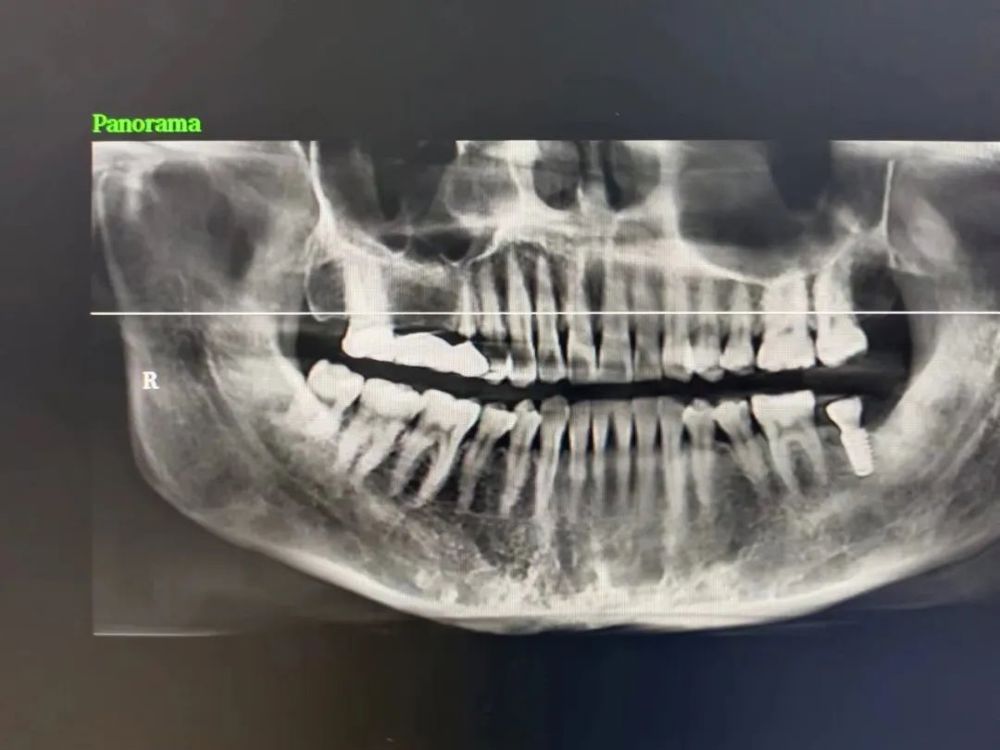

案例二

种植前 种植后